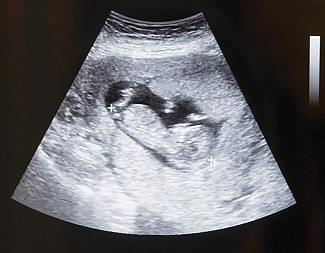

Wyrażamy zaniepokojenie wypowiedzią Premiera Mateusza Morawieckiego dla Tygodnika WPROST, deklarującą ponowne wprowadzenie aborcji eugenicznej do polskiego porządku prawnego. Wypowiedź ta pozostaje w kontrze do Pańskiego stanowiska, wyrażającego sprzeciw wobec legalności aborcji eugenicznej w Polsce